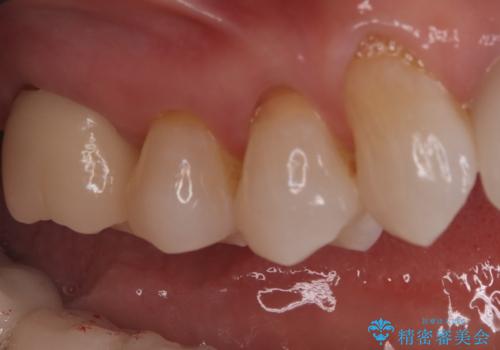

オールセラミッククラウンによる修復: 根管内が清潔に封鎖されたことを確認した後、土台を立てて歯の形を整えました。最終的な被せ物には、金属を一切使用しないオールセラミッククラウンを選択。天然歯のような透明感を再現し、高い適合性によって再び虫歯になるリスクを抑えています。

今回の治療により、詰め物が取れた根本的な原因が解消され、見た目も美しく、長持ちする奥歯を再建することができました。